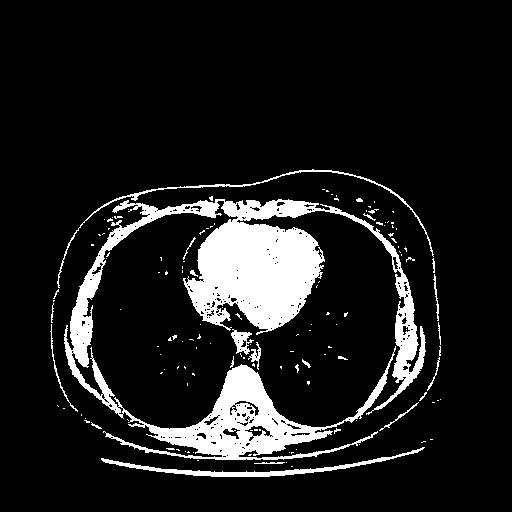

Original NATIVE CT scan (input)

Full window (WL 1023.5, WW 4095 β†’ Low βˆ’1024, High +3071)

Actual HU range: [-1024.0, 3071.0]